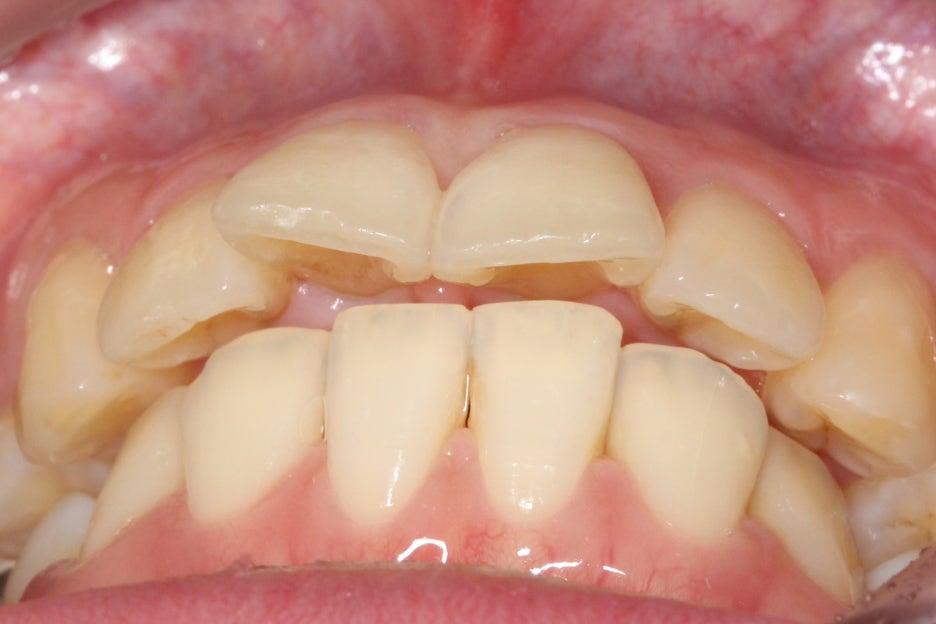

overjet 사진을 보시면

일반적인 Case와 달리

윗니와 아랫니의

돌출차이가 심하고

아랫니가 깊게

물리는 모습을 확인할 수 있습니다.

전치에서 구치까지 이어지는

협측 사진을 보시면 중절치의

튀어나온 모습을 명확하게

확인할 수 있습니다.